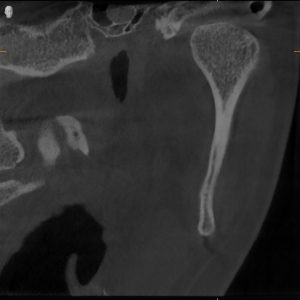

MRI confirmed bilateral disc displacement without reduction — both jaw joints had discs that had slipped out of position, causing compression and inflammation.

Clinical & Radiographic Findings

- Bilateral disc displacement without reduction

- Restricted opening (31 mm → improved to 47 mm)

- Myofascial tenderness and deep bite

- Significant parafunctional clenching pattern

Bilateral TMJ dysfunction with disc displacement and muscular hyperactivity.